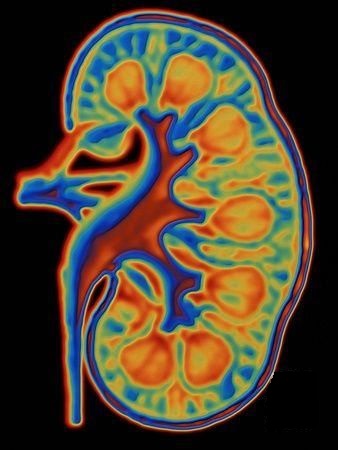

Что показывает КТ почек и надпочечников – с контрастом и без него

Нативная КТ диагностика почек и мочевыводящих путей применяется в качестве дополнительного метода, когда рентгенография недостаточно информативна. В зависимости от диагностических целей выделяют 3 разновидности процедуры – нативная, с болюсным контрастированием мочевыводящего тракта, усилением мочевого пузыря.

КТ почек без контраста – что покажет

Нативная компьютерная томография лучше визуализирует плотные камни внутри лоханки и мочеточника. Контрастное усиление повышает качество сигнала. Аналогичную КТ-картину создает конкремент. Чтобы исключить слияние сигнала для верификации плотных камней достаточно нативной компьютерной томографии почек и мочевого пузыря (без контраста). Дополнительное усиление требуется для определения кист почек на кт, патологических образований.

Бесконтрастное обследование информативно в нескольких плоскостях. Визуализация конкремента в аксиальной проекции недостаточно достоверна. Повышают информативность сканирования сагиттальные и коронарные срезы. Обнаружение светлых теней высокой плотности в мочеточнике не обязательно свидетельствует о мочекаменной болезни.

КТ почек с контрастированием

Процедура обследования кт почек с контрастным веществом проводится болюсно. Предполагает выполнение томограмм в разные фазы распределения контраста – артериальную, венозную.

Контраст при выделении через мочевыводящие пути усиливает видимость лоханки, мочеточника, что позволяет выявить гидронефроз (отечность почечной ткани), расширение чашечно-лоханочной системы, причины непроходимости мочеточника.

Расшифровка КТ почек – что показывает:

Спиральная компьютерная томография почек – показания

Мультиспиральная КТ характеризуется высокой разрешающей способностью за счет выполнения сканов через расстояние в несколько миллиметров. Возможности современных аппаратов позволяют проводить сканирование через каждые 0,5 мм с последующей трехмерной реконструкцией. С помощью аппаратуры хорошо делать кт сосудов почек, позволяющее обнаружить раки на начальном сроке.